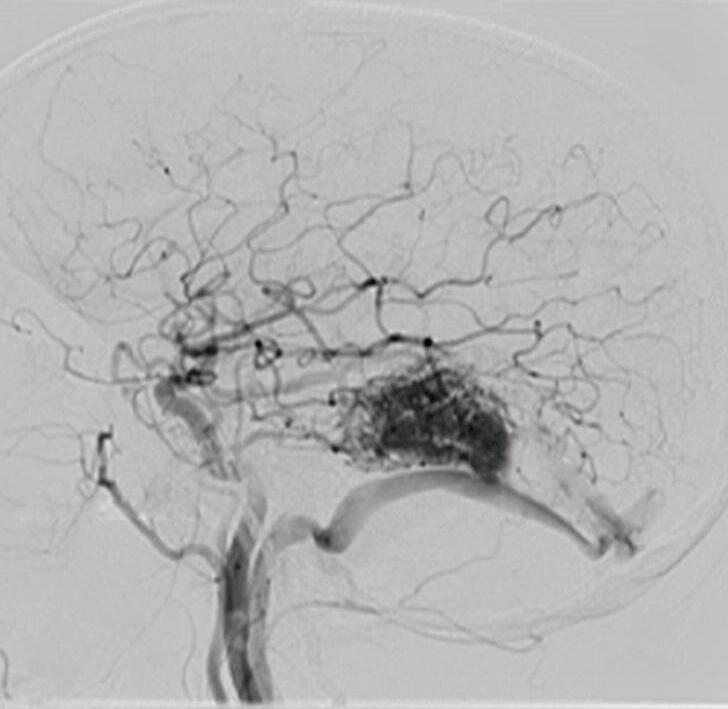

Com relação ao fluxo no interior do nidus, alguns autores classificam-nas em alto fluxo (Fig. 1-8) e baixo fluxo (Fig. 1-9). São consideradas de alto fluxo aquelas em que a opacificação após injeção de contraste ocorre apenas na malformação, em contrapartida, nas de baixo fluxo, ocorre opacificação da MAV e de outras artérias normais do mesmo território vascular. Exemplificando as lesões de alto fluxo temos as malformações arteriais, as malformações arteriovenosas e as fístulas arteriovenosas, enquanto as lesões de baixo fluxo são representadas pelas malformações venosas, linfáticas e capilares.25

Fig. 1-8. (a-c) RNM T1 com contraste, cortes sagital (a), coronal (b) e axial (c) demonstrando MAV não rota com nidus localizado no lobo occipital à esquerda (setas longas). (d) Arteriografia digital cerebral com injeção de contraste via carótida direita (AP) mostrando a contribuição da carótida direita na irrigação da MAV contralateral. (e,f) Com injeção de contraste via carótida esquerda, em Perfil e AP respectivamente, observa-se nidus compacto nutrido por ramos da artéria cerebral média à esquerda e a veia de drenagem precoce se dirigindo para o seio sagital superior. Projeções em AP (g) e em perfil (h) demonstrando a contribuição do sistema vertebrobasilar por meio de ramos distais da artéria cerebral posterior à esquerda e drenagem para os seios sagital superior e sigmoide à esquerda (setas curtas).